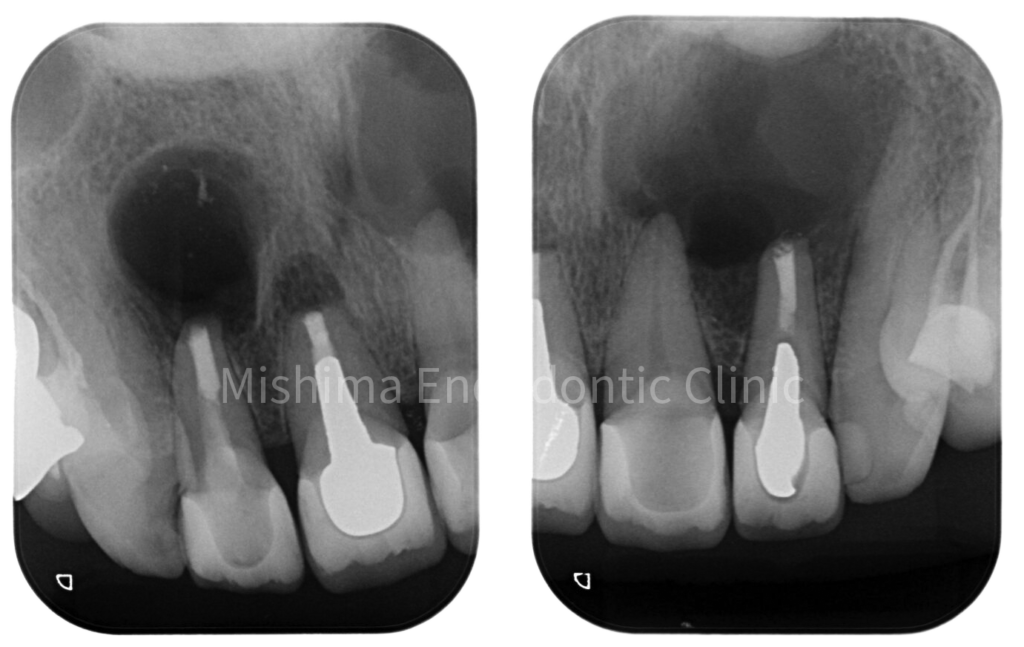

術直後